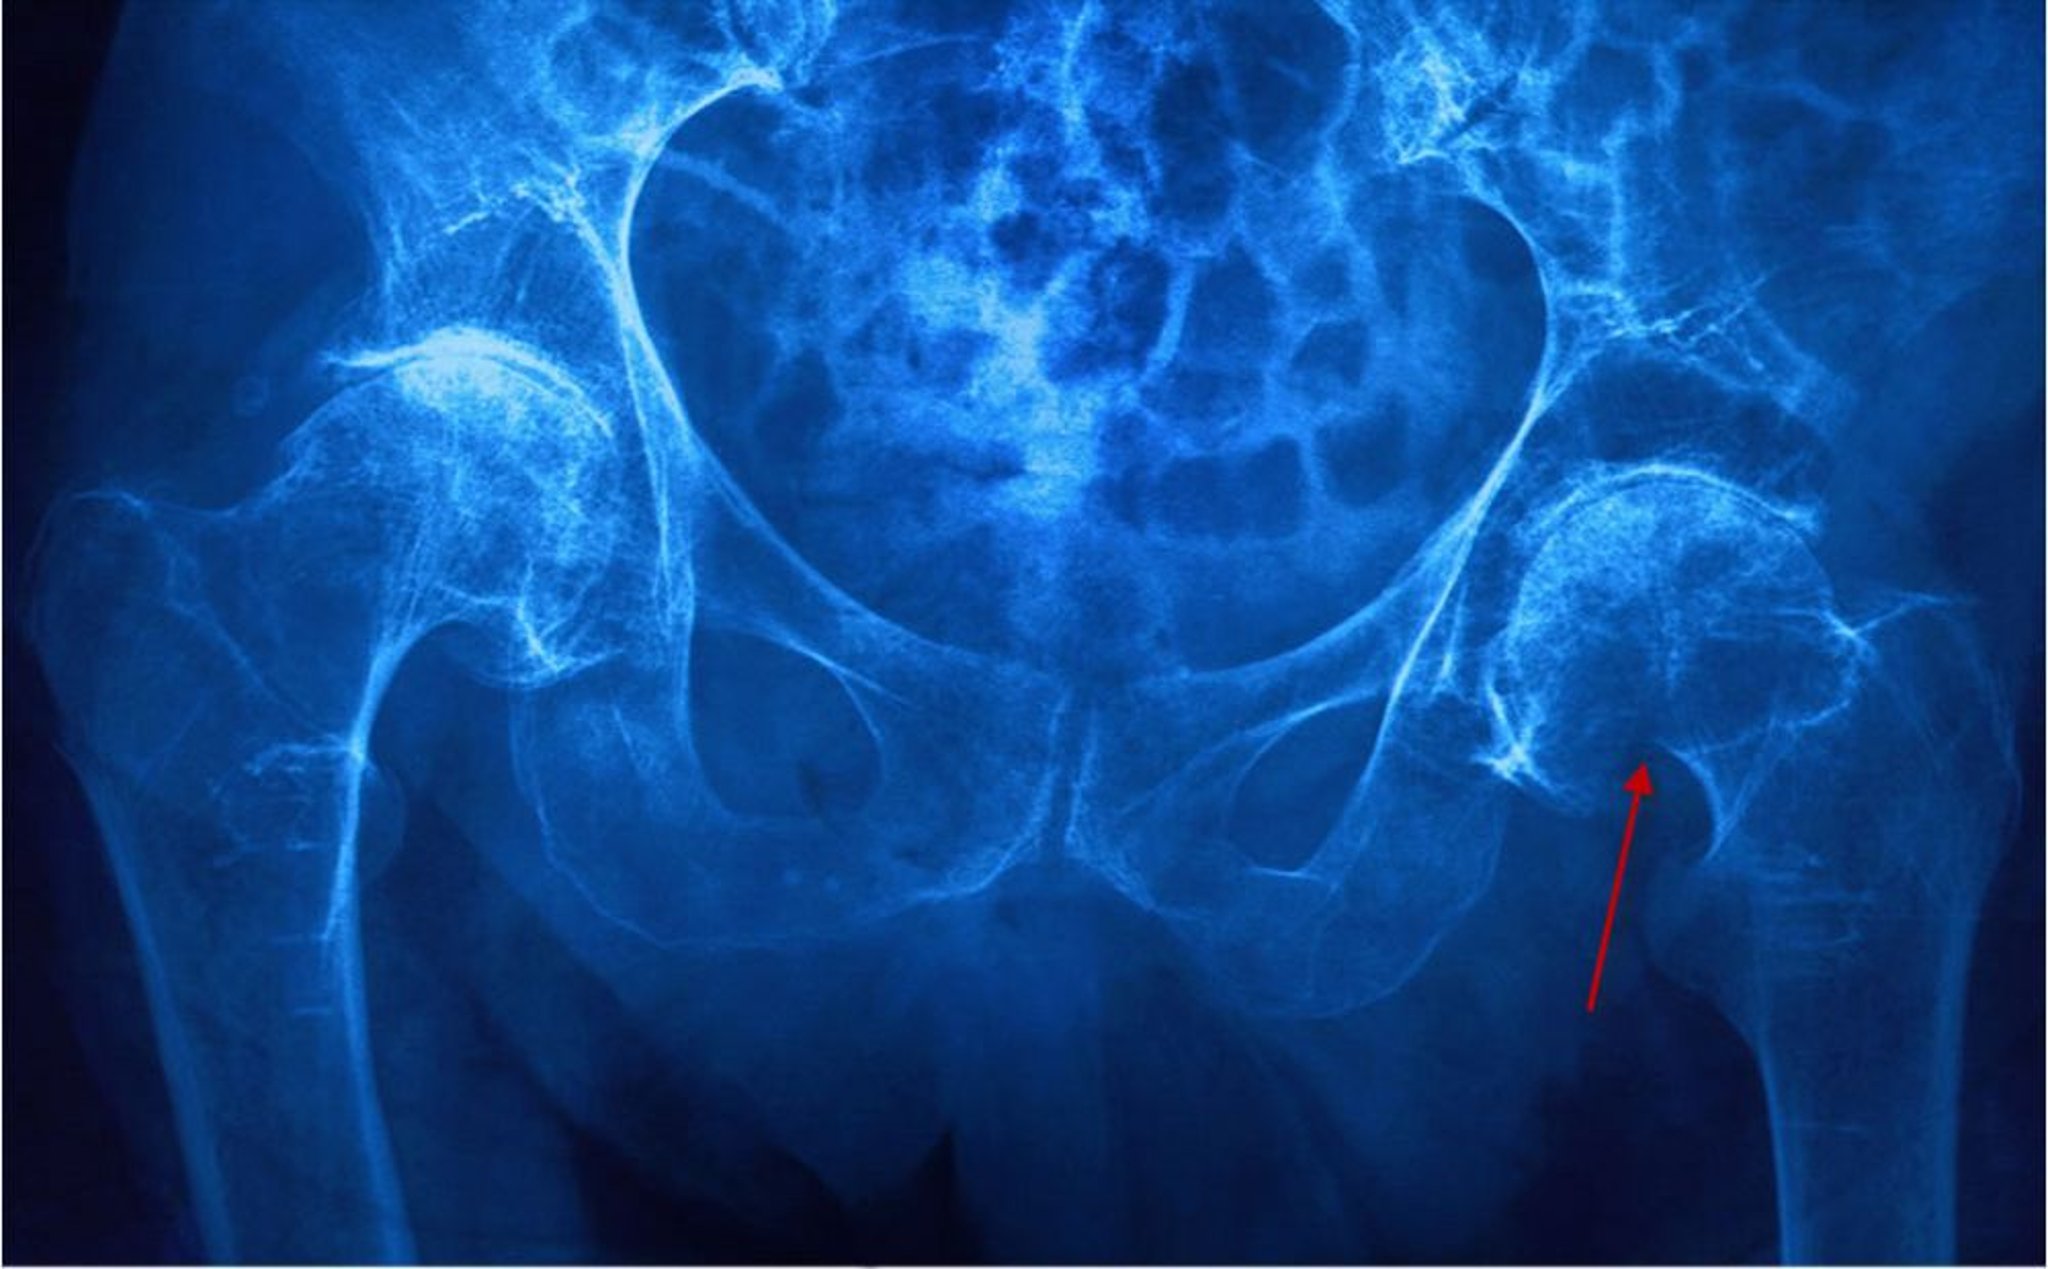

La diagnosi di una sospetta frattura dell'anca inizia con una radiografia del bacino in anteroposteriore e una proiezione laterale diretta. Se viene identificata una frattura, devono essere eseguite le radiografie dell'intero femore. La tenue evidenza di frattura (p. es., come quando le fratture sono minimamente scomposte o ingranate) può includere irregolarità nella densità trabecolare o della corticale ossea del collo femorale. Tuttavia, le radiografie risultano a volte normali, in particolare nei pazienti con fratture sottocapitate o in caso di grave osteoporosi.

Se una frattura non è visibile sulle radiografie ma è sospettata clinicamente, la risonanza magnetica è lo studio di imaging preferito. La risonanza magnetica è più sensibile della TC, la quale può non rilevare fino al 30% delle fratture acute.